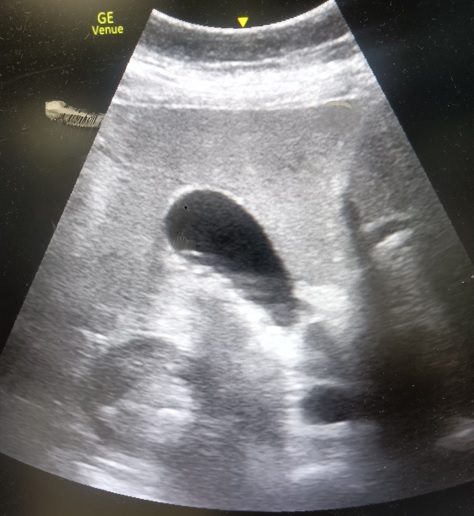

Se realiza ecografía clínica (POCUS) en la que se evidencia vesícula biliar con múltiples cálculos Murphy ecográfico positivo, vía biliar no dilatada. Además en riñón derecho se objetiva imagen cálcica de 1 cm con hidronefrosis grado II. No presenta líquido libre, aorta dentro de parámetros normales.

Este caso destaca la utilidad de la ecografía en urgencias para diferenciar simultáneamente causas biliares y renales de dolor abdominal, optimizando decisiones diagnósticas y la coordinación con Atención Primaria.